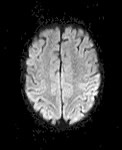

Diffuse MRI shows signal changes caused by the diffusion of water molecules in tissues. Such an image is relatively independent of the relaxation times T1, T2 and the density of the proton nuclei (PD). Diffuse imaging is used mainly in the evaluation of pathological conditions of the brain (age of ischemic brain injury, traumatic changes in the brain, assessment of the cell composition of brain tumors or changes due to Alzheimer's disease, autism, schizophrenia, etc.). The direction of diffusion can be completely random in all directions (eg in cerebrospinal fluid or gray matter of the brain) or limited to only some directions (eg in the white matter of the brain diffusion predominates in the direction of long axonal fibers), where omnidirectional diffusion is prevented by walls. The direction of diffusion can be determined by scanning the selected tissue layer multiple times in several directions. The individual directions of the image are obtained by changing the orientation of the magnetic gradients. Each gradient direction then shows a different diffusion direction. In practice, the direction of diffusion is calculated from at least 6 directions, but usually from 12 to 256 directions. The result of diffusion imaging can be a gray scale map of diffusion size (DWI method - Diffusion Weighted Imaging) or a color map of the brain (DTI method - Diffusion Tensor Imaging), where individual colors determine the individual directions of diffusion in a given area.

DWI method - Diffusion Weighted Imaging

In DWI, the intensity of each element of the image (voxel) reflects the diffusion rates of water in the area. since water movements are highly dependent on thermal conditions and the cellular environment itself, we should be able to observe changes in a given tissue thanks to DWI and therefore to observe early changes indicating pathological conditions. To illustrate, DWI is more sensitive to the early pathological changes accompanying stroke than traditional MRI. DWI is most suitable for the description of tissues in which the isotropic movement of water dominates, ie gray matter in the cerebral cortex, large brain nuclei or in the body, where the rate of water diffusion appears to be approximately the same in all directions.